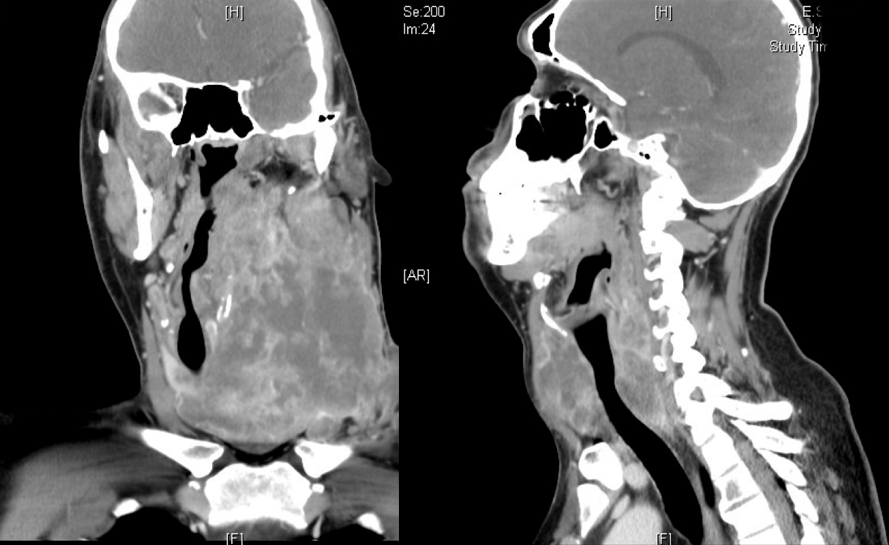

A giant mass in the neck of a young men: a case of anaplastic thyroid cancer

A 29-year-old man presented with a 4-month history of a mass in the left lateral region of the neck that was painful to palpation. Growth of this mass caused a change in his tone of voice, dysphagia to solids that progressed to liquids, and dyspnea. He also referred a weight loss of 3 kg. He had no previous medical history. Physical examination of the neck showed a left ganglionar conglomerate, which covered all areas of the neck and the supraclavicular hollow and that extended to the opposite side with limitation of cervical movement. There was involvement of the left cranial nerves XI and XII. Laboratory tests revealed a TSH serum level of 5.19 uU/ml (0.27-4.2 uU/mL), a free T4 level of 0.80 ng% (0.93-1.7 ng%), and a thyroglobulin of 12.2 ng/ml (1.40-78.0 ng/ml). Histopathological analysis showed an anaplastic carcinoma of the thyroid. Due to the great extension of the disease and metastasis to the lung demonstrated by tomography, it was decided to initiate a chemotherapy regimen based on cisplatin and doxorubicin. Despite this treatment, the patient died three months later. Anaplastic thyroid cancers are extremely aggressive undifferentiated tumors with rapid progression and very poor outcome with a median overall survival of less than six months. For unresectable disease in patients who desire active therapy, radiation and/or chemotherapy is the preferred option for local control of the disease. Palliative care is important in this setting and should be added to any treatment plan.